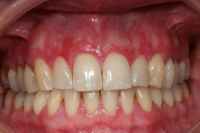

En volymökning av mjukvävnaden kring tänderna som är associerad med intag av läkemedel tillhörande grupperna antiepileptika, immunosuppressiva läkemedel och kalciumblockerare.

Inflammation är den utlösande faktorn som driver tillväxten av mjukvävnaden därför är plackkontroll av största vikt.

Förekomst av gingivala hyperplasier med djupa tandköttsfickor och svåra hygienförhållanden som följd.